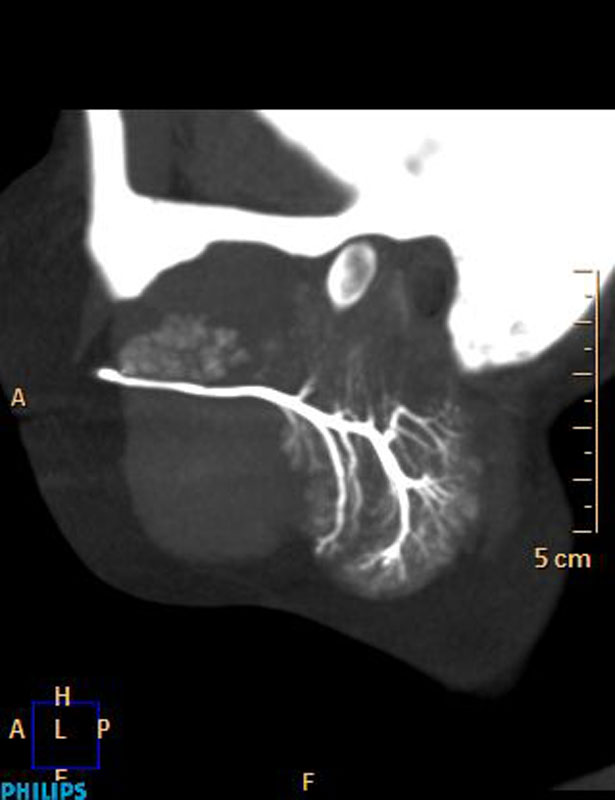

Внедрен современный протокол диагностики эпилептогенных очагов головного мозга — протокол SISCOM (Subtraction Ictal SPECT Co-Registered to MRI)

Апробированы современные методики в диагностике заболеваний слюнных желез, которые позволяют с высоким пространственным разрешением и возможностью построения 3D реконструкций оценить наличие нарушения проходимости протоков слюнных желез